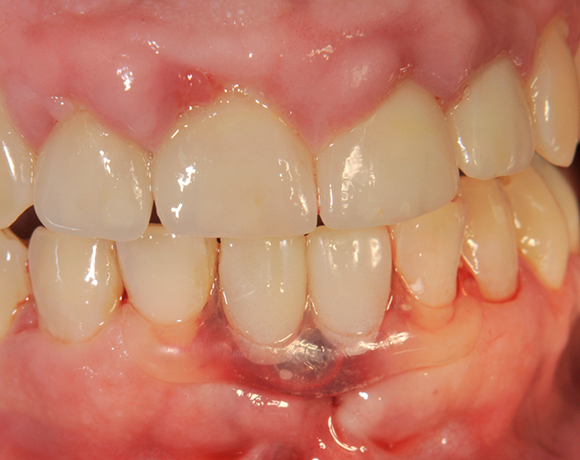

Die Keramikimplantate der Fa. Dentalpoint lassen sich auch zur Sofortimplantation verwenden. Das bedeutet, dass nach Extraktion nicht beherdeter Zähne direkt die Implantate gesetzt werden können.

Im vorliegenden Patientenfall wurden die beiden nicht erhaltungswürdigen, mittleren Unterkieferschneidezähne durch zwei Vollkeramikimlpantate ersetzt.